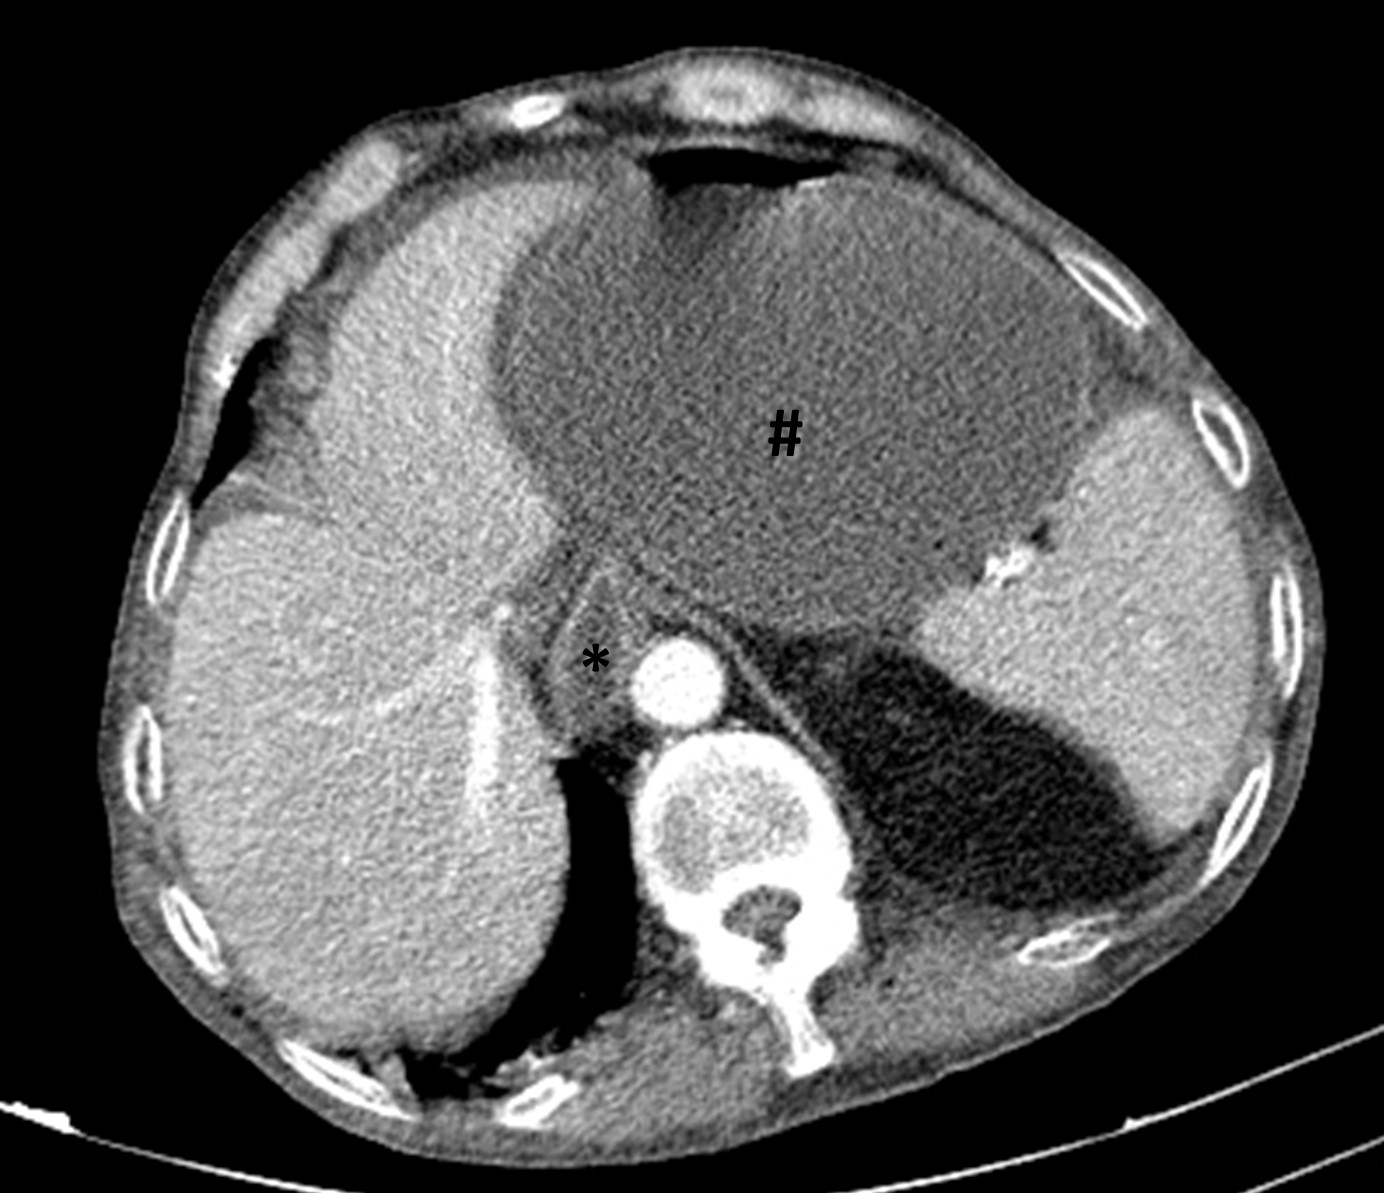

A tangential abdominal radiography was obtained, in this context, and a gas level on the non-dependent portion of the abdomen was identified (Figure 1). This finding raised the suspicion of pneumoperitoneum and, therefore, a CT was performed. On CT, a markedly distended stomach, as well as a distended oesophagus and free abdominal fluid were identified, implying an obstructive event (Figure 2). The inferior portion of the stomach and some intestinal loops were contained on the right inguinoscrotal hernia, making this the most probable cause for the obstruction (Figure 3).

Very few cases have been reported of inguinal hernias containing stomach, with the most cases occurring before 1980.2 In this particular case, the inguinal hernia was causing a massive gastric distention (Figure 2), indicating a gastric obstruction outlet, impeding gastric emptying. It is thought that long-standing traction of the greater omentum in the context of a long-standing hernia may draw the stomach into the hernial sac. Chronic obstructive pulmonary disease was also suggested as a part of the pathogenesis of gastric herniation although very little direct evidence was found to support this theory.1